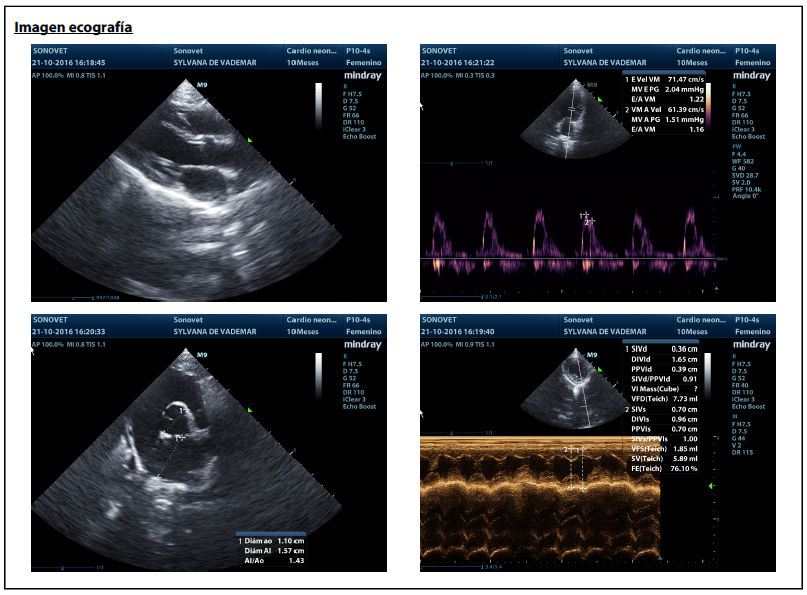

La mejor prueba para diagnosticar HCM es una ecocardiografía, realizada por un experto. En esta prueba se puede llegar a medir detalladamente el grosor de las paredes del corazón para confirmar o descartar la presencia de hipertrofia.